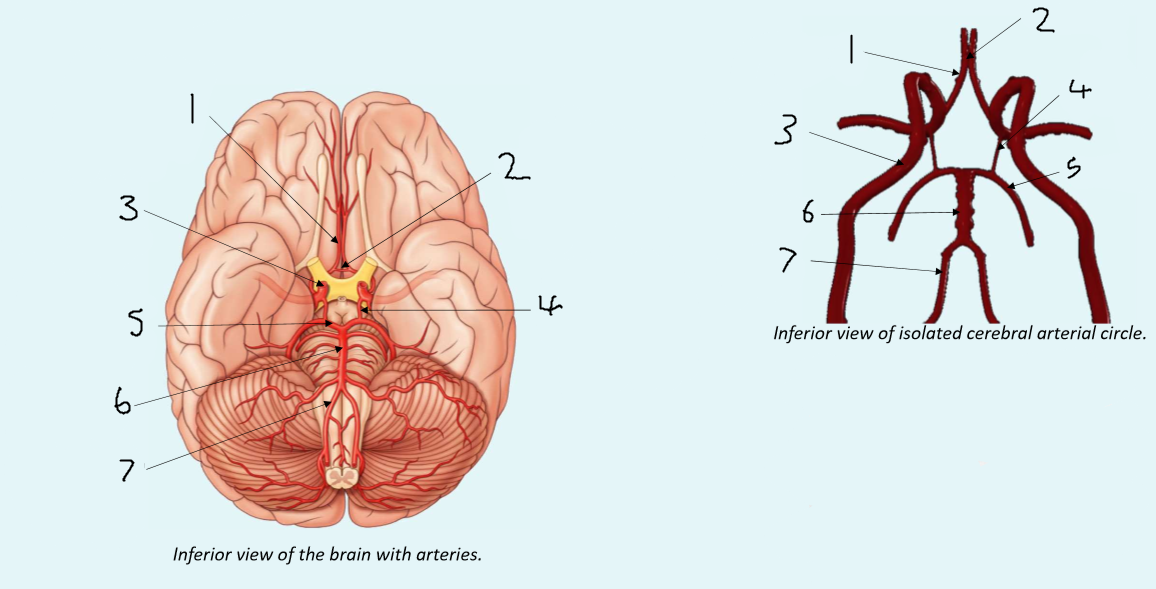

What is 1?

anterior cerebral artery

What is 2?

anterior communicating artery

What is 3?

internal carotid artery

What is 4?

posterior communicating artery

What is 5?

posterior cerebral artery

What is 6?

basilar artery

What is 7?

vertebral artery